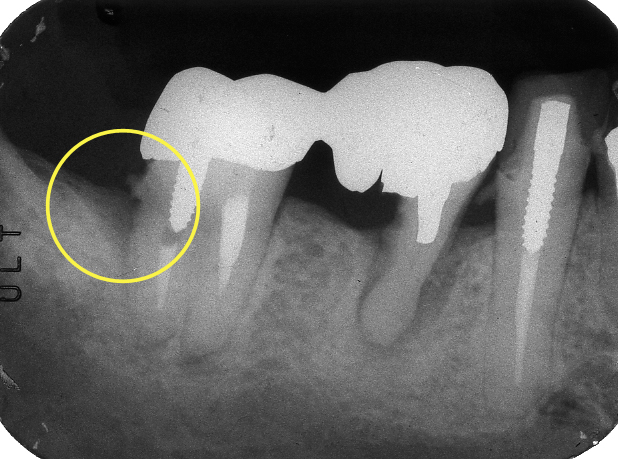

丸印の部分が,歯周病が進行して歯を支えている歯槽骨が溶けてしまっているところです。歯石が着いていてレントゲンでも根の表面が粗造になっていることがわかります。また,歯石の少し上には被せ物の縁がありますが,それも根っこからはみ出てて適合が悪いことが分かります。歯石も適合の悪い被せ物も,歯周病の原因であるプラークを停滞させる要因になります。

また,手前の歯(丸印の付いた歯の右に写っている歯)は昔に分割して,悪い方の根っこだけ抜歯する治療を受けています(ヘミセクションといいます)が,残した根っこの全周にわたって歯周病が進行していました。